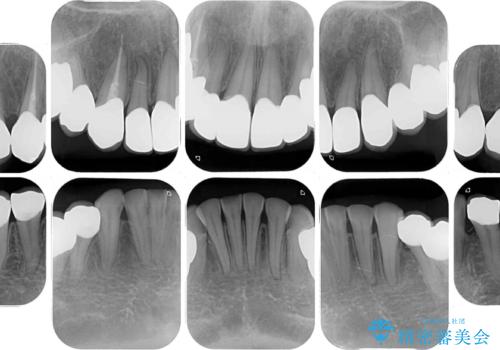

- 一時期の拒食症に伴い歯が酸で溶けてボロボロになってしまったとのことで来院された患者様です。

酸によりエナメル質の大半が溶けており、下顎前歯以外は酷いむし歯のような状態でした。

当初はほとんどの歯をむし歯治療のようにオールセラミッククラウンにて補綴治療を行う予定でしたが、仮歯に置き換えた時点で、口元の突出感や下顎前歯の叢生が気になるとのことで、上下左右の第一小臼歯4本を抜歯したワイヤー装置での抜歯矯正を行うこととしました。

矯正治療終了後に、残った歯をオールセラミッククラウンにて補綴治療を行うこととしました。